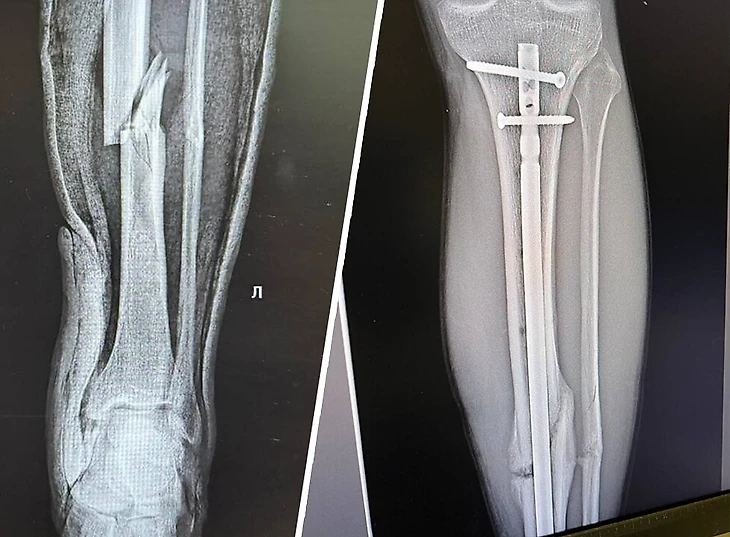

17 ноября 2024-го «Амкал» рубился с «Динамо» в шоу-матче. На 15-й минуте амкаловский форвард Степан Костюков вышел на один на один, но не забил – вратарь Андрей Кудравец упал всем весом на ногу Костюкова. Форвард получил открытый перелом.

Всего мне провели четыре операции. В день перелома – собрали кость и поставили спицы. Операция длилась минут 50-60, потому что хирургу не удавалось сложить пазлом отколовшиеся части кости. Помню, как врач выдохнул: «Фух, получилось».

Но самой сложной была вторая операция, она длилась примерно три часа. В большую берцовую кость ставили штифт. Разрезали колено, собственную связку надколенника (она чуть ниже чашечки), просверлили сверху большую берцовую кость и молотком вогнали штифт. Звуки были как на стройке. Врач использовал обычную дрель Makita – такую же, как для ремонта. Я был в сознании, отключали только ноги. Штифт до сих пор в ноге – у врачей нет единого мнения, нужно ли его убирать.

Последняя на данный момент операция была в июле – к этому моменту я уже бегал. Врачи сняли болты, которые фиксировали штифт в ноге. Места, где стояли болты, больше всего болели. Спустя полмесяца стало намного легче.